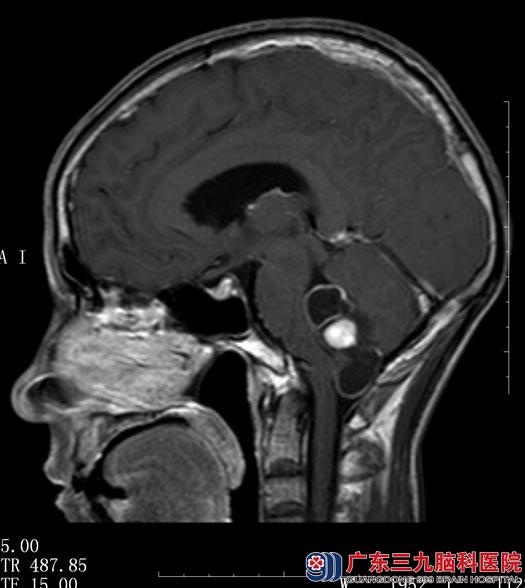

广东三九脑科医院核磁共振检查结果:“右侧小脑半球囊实性占位,实性部分直径约2cm,考虑血管母细胞瘤”。

综合神经外科鲁明主任阅片后认为:结合患者病史、症状、体征及头颅MR检查,考虑右侧小脑半球血管母细胞瘤,肿瘤呈囊实性,对小脑半球及脑干有压迫,手术指征明确。

▲手术前